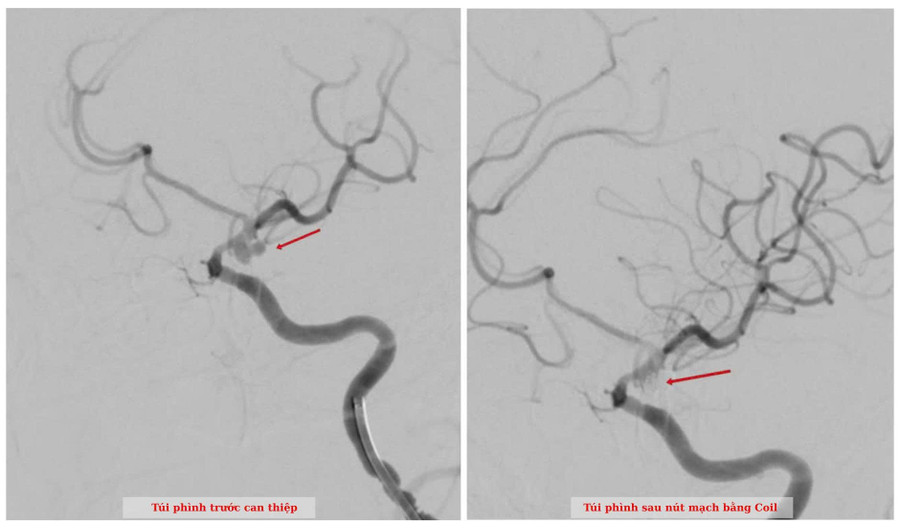

Nhận định đây là ca bệnh cực kỳ nguy kịch, ê-kíp bác sĩ đã nhanh chóng đặt ống thở và tiến hành chụp mạch máu khẩn. Kết quả xác định túi phình nằm ở vị trí quan trọng của mạch máu não và đã vỡ.

Sau khi hội chẩn, các bác sĩ quyết định thực hiện thủ thuật can thiệp mạch để xử lý túi phình. Ca can thiệp kéo dài gần hai giờ và kết thúc thuận lợi.